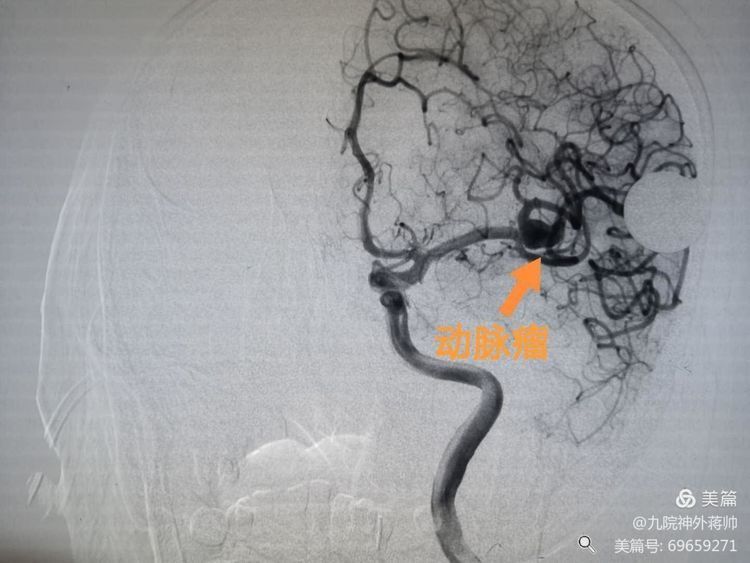

询问患者老伴后得知徐老师既往有高血压多年,医生结合颅脑CT结果,高度怀疑患者颅内动脉瘤破裂。刘展会主任急诊为徐老师行全脑血管造影术,术中证实患者存在十分复杂的颅内动脉瘤,动脉瘤位于左侧大脑中动脑的分支,同时发现动脉瘤呈宽颈,存在子瘤,并且累及大脑中动脑分支上干。

因动脉瘤复杂,单纯行动脉瘤栓塞难度很大,如需再植入支架,更是难上加难。刘展会主任结合患者病情,制定了详细的手术策略及应对措施。经过三个多小时的连续奋战,刘展会主任、张西安副主任医师、蒋帅医师联合为徐老师实施“支架辅助下左侧大脑中动脉动脉瘤介入栓塞术”,手术顺利。